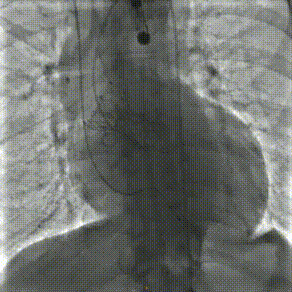

主动脉根部造影

释放后造影